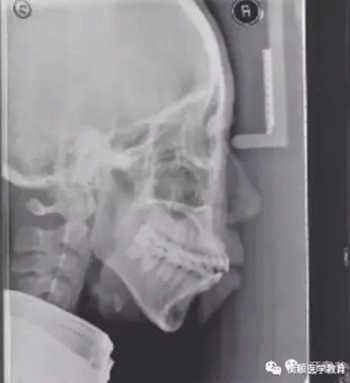

圖2 治療前頭顱側(cè)位片